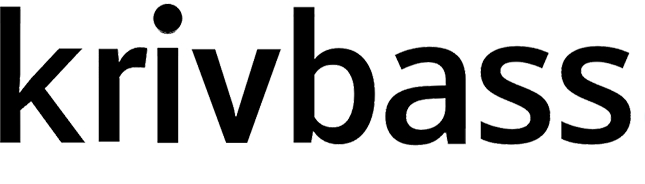

Після пострілів вдалося вижити лише 3 місячному цуценяті, куля потрапила у зону ребра, а от другій патрон потрапив прямо у серце. Від отриманого поранення собака померла на місці.